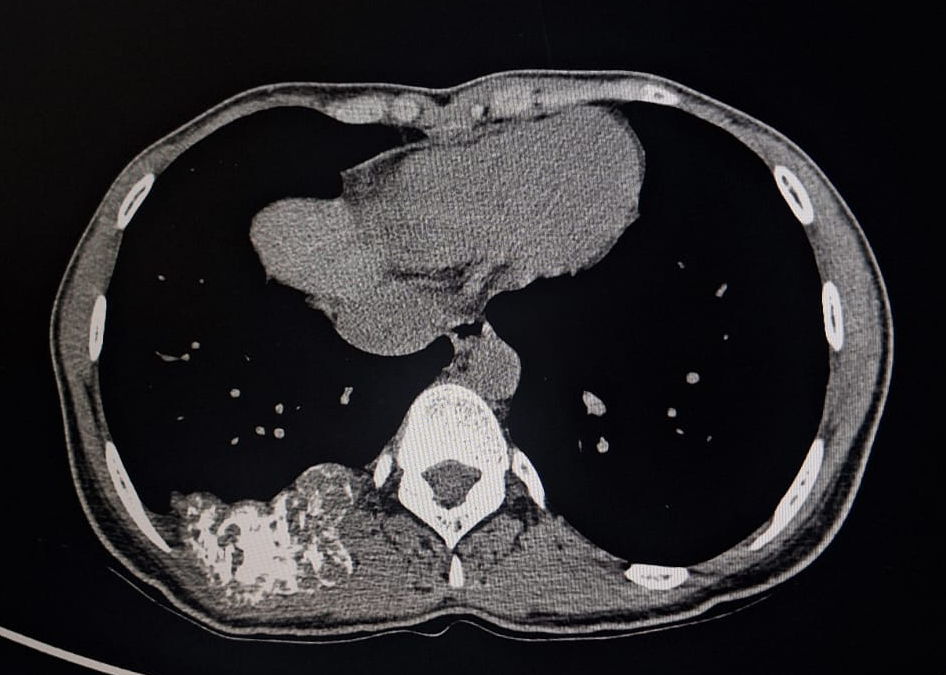

A young 23 year old female first presented in 2015 with complaints of right-sided chest pain and swelling. A thorough clinico-radiological evaluation was done and general surgeon consultation sought. Imaging revealed an expansile lytic lesion of the right 9th rib (Fig 1). Other long bone x-ray evaluation was done and found no abnormalities. We planned for excision biopsy of 9th rib and patient underwent surgical excision (Fig 2). Histopathological examination confirmed a benign intraosseous hemangioma(Fig 3). Post-operative recovery was uneventful. 6 monthly followed by yearly radiological follow-up was being done till pre-covid period. Patient lost to follow-up during 2020-2022 Covid-19 period.

• 2015: Expansile lytic lesion of right 9th rib with cortical thinning (Fig 1).